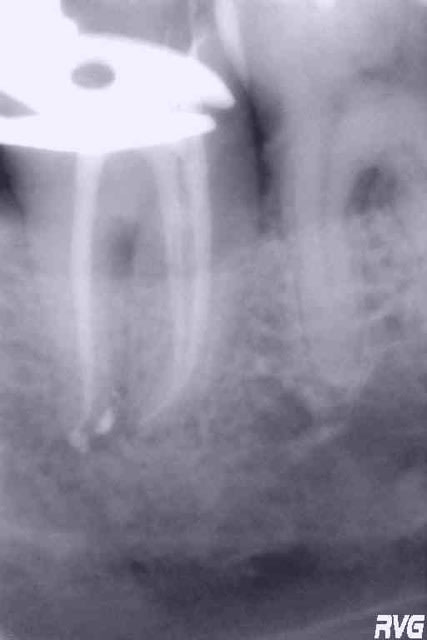

d'apres vous, c'est quoi?

je fais quoi?

sinon entre temps, tentative de RTE : peux pas mieux faire à mon niveau.

cementose ou osteification peut-être en rapport avec la perméabilité de l'apex ?

Salut Sbire, la 6, si asymptomatique et pas de projet prothétique, je l'aurais laissée comme ça.

Si projet pro, RTE, puis temporisation après reconstitution collée.

Pour l'espace entre 6 et 7, je vérifierais la présence d'une éventuelle sur-occlusion sur 7, mais la lésion est probablement dûe à l'absence de point de contact.

choipeaux c'est pas le septum qui pose problème, c'est l'image apicale ...

Pour ton image apicale, j'ai parlé de RTE, il faut lire toutes les lignes.

La RTE est un peu limite, c'est vrai, mais si tu n'a pas pu faire lieux personne ne te jettera la pierre (d'Arkansas).

Ce qui manque dans ton exposé c'est le temps entre les deux clichés.

Si tu as pris ton temps pour désinfecter, si tu as obturé sous condensation, tu peux espérer, malgré le cliché, avoir assaini un delta apical aux canalicules comblés par très peu de ciment. On peut rêver, du moins espérer.

Radio à 2 mois, puis 4.

Si régression de l'image apicale, prothèse après avoir fait objectivé l'amélioration par le patient et s'il accepte le risque d'une récidive possible à LONG TERME.

Personnellement je traiterais les image de densification osseuse péri-apicale... par le mépris. :)

Mark, le temps entre les deux clichés est celui qui sépare les deux messages ; le localisateur me signale l'apex sur les deux racines mésiales, mais effectivement pas sur la racine distale que je n'ai pu explorer plus avant...obturation par thermocompactage, petites sensibilités sur les trois canaux lors de l'obturation...

C'est clair que tu devais avoir un delta apical au niveau de la racine distal.

Un système B (ou touch'N'heat) par exemple aurait surement pu l'obturer.

Suis d'accord avec Mark je ne me préoccuperai pas outre mesure de la densification osseuse.. Eventuellement instaurer un controle radio régulier pour te rassurer...